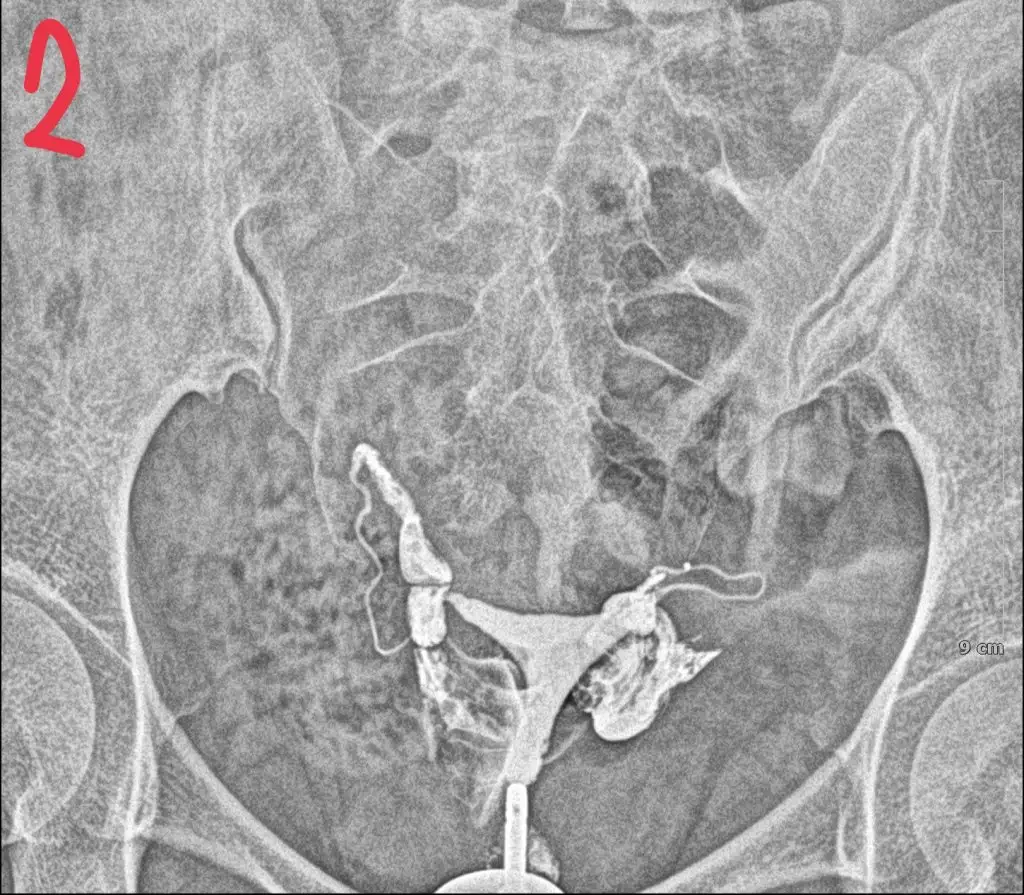

tüp bebek merkezine yönlendirdi . Orada daha detaylı kan tahlili muayene yapıldı adet bitimi hsg çekindim . Çekindiğim gün işlem başında doktor iki tüpün de tıkalı canım dedi ben ağlamaya başladım ağlama sakinleş ilaç ile açmaya çalışacağım eğer olmazsa ameliyat olursun demişti . İşleme 4-5 kez tekrarladık . Sonra iyi kötü bi gidiş oldu . O zaman ki ilgilenen doktora olanları anlattım böyle birşey imkansız tüpler açık o ara kasmışsındır dedi ama hiç kasmadım inanın ki . 6 ay dene olmazsa gel dedi 6 ay sonra gittim o doktor yoktu . Başka doktora geçtim oda sızıntının yeterli olmadığını hala tıkalı olduğunu ve içeriye iyi bir müdahale yapılması gerektiğini söyledi . Ameliyat önerdi . Laparoskopi olacağım ayın 27 sinde . Sonrasında aşılama yapmaya başlıcaz olmazsa